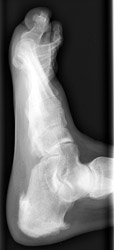

REITER'S

ARTHRITIS:

1. Distribution:

The MTP joints, first IP, and the calcaneus are the most frequently involved

joints in the foot. Initially there is a monoarticular involvement which may

lead to the misdiagnosis of septic arthritis. The calcaneus is involved in

50% of patients.

2. Erosion pattern:

Like psoriatic arthritis, ill-defined erosions with uniform joint loss and

bone proliferation are observed. In addition, periostitis along bone shafts

is present. There may be fusiform soft tissue swelling involving a single

digit, giving appearance of a sausage. Early juxta-articular osteoporosis

is present however there is usually a re-establishment of normal mineralization.There

is erosion and bone production at the attachment of the Achilles tendon and

the plantar aponeurosis. Soft tissue swelling and fluffy periostitis involving

the distal ends of the tibia and fibula are characteristic for ankle involvement.